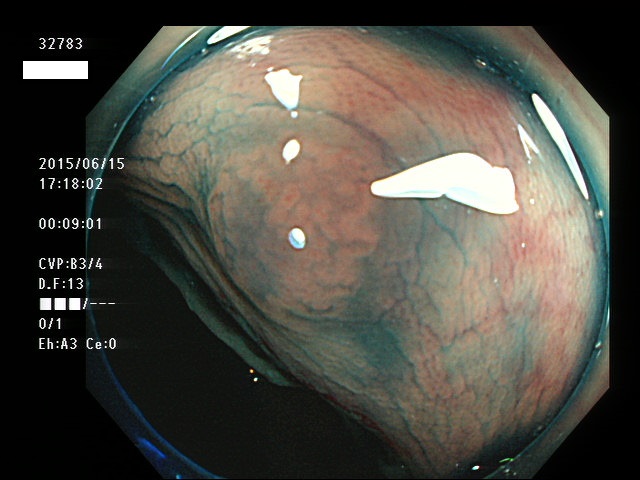

上記100名より抽出した平坦・陥凹型腺腫(=癌化の危険が高いが見落としやすい病変)の内視鏡写真

腺腫発見率 57% (カルテ番号32700〜32799の100名の方の検査結果で集計)

以下のカルテ番号の方に腺腫(Adenoma,Group3〜5)が見つかりました

32768 32770 32771 32772 32773 32774 32775 32777 32778 32780 32782 32783